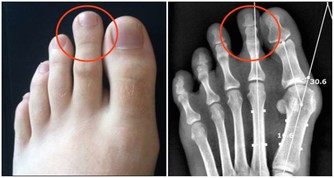

1.指甲表面有凸起的棱線,或是向下凹陷。中醫認為「肝主筋」,指甲是「筋」的一部分,所以毒素在肝臟蓄積時,指甲上會有明顯的信號。